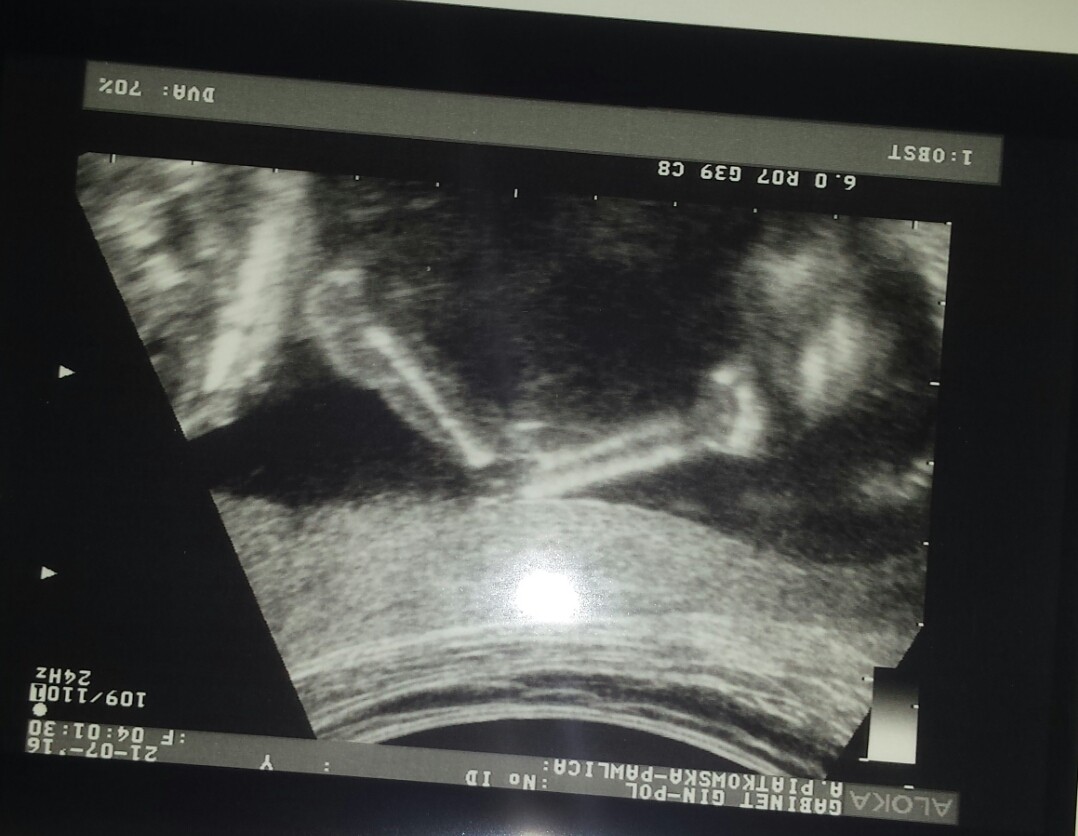

Oto obiecane zdjecia :)

Jest główka i ten nasz siusiak :) hihi. Mam filmiki nagrane z USG na płytce i na jednym otwieral i zamykał buźkę a na końcu język pokazał :D:D:D